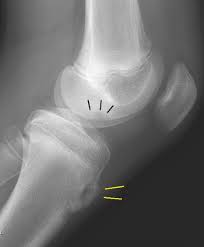

Diagnosis is made clinically with an enlarged tibial tubercle and supplemented with radiographs of the knee that reveal irregularity and fragmentation of the tibial tubercle. Osgood-Schlatter disease is an overuse injury of the knee common in growing adolescents. Osgood-Schlatter is a common disease with most cases resolving spontaneously with skeletal maturity.

Osgood Schlatter Disease Collection Of Plain X Rays